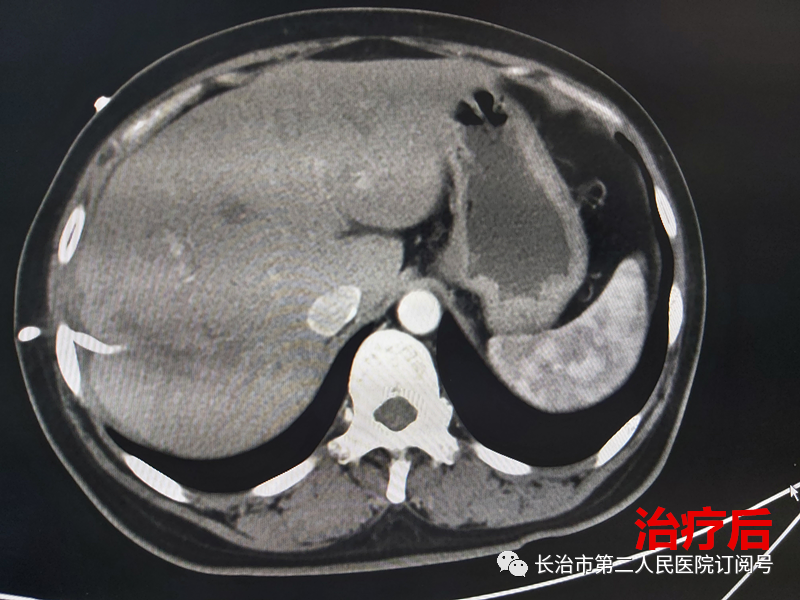

原女士现年44岁,因“纳差伴恶心、呕吐5天”,5天前受凉感冒后出现食欲减退,伴恶心、呕吐、发热,最高达39.2℃,伴右上腹痛、腹胀,无反酸、烧心、心慌、气短等,曾自行口服“阿莫西林”,肌注“地塞米松”治疗,未见明显好转,来到长治二院入住介入血管外科。经B超及肝脏平扫+增强CT检查发现,患者体内有巨大(多个)肝脓肿正在“作祟”。

立即给予行抗感染治疗的同时积极术前准备并于当日给予行“经皮经肝肝脓肿穿刺置管引流术”,术中引出灰黄色浓稠脓液约100ml,并留取脓液行细菌培养+药敏检查。

图片

细菌培养结果提示“肺炎克雷伯菌”,脓液经充分引流和抗感染及对症治疗后,患者腹痛、腹胀、发热、乏力症状渐好转,“经皮经肝肝脓肿穿刺置管引流术”后恢复良好,顺利出院。